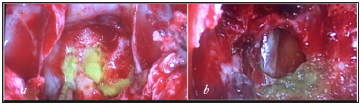

A 36 -year-old female was admitted for three weeks of clear watery discharge from the right nostril, which was aggravated in prone position. The patient denied any recent trauma. A review of systems was negative except for headaches and nasal discharge. The nasal fluid tested positive for beta-2 transferrin, indicating that the fluid was CSF. Brain MRI revealed that the sphenoid sinus was filled with Cerebrospinal Fluid (CSF) and sagittal T2 weighted MRI revealed a fistula tract from prepontine cistern to sphenoid sinus (Figure 1). There was no evidence of benign intracranial hypertension. Computed tomography cisternography revealed that the contrast material passed from the prepontine cistern into the sphenoid sinus through this bone defect in the clivus (Figure 1). Before surgery, a lumbar puncture was performed to administer 0.25mL of 10% fluorescein with 10mL of Cerebrospinal Fluid (CSF) to help visualize CSF leaks during surgery and to ensure there was no leak after reconstruction of the defect. The patient underwent endoscopic trans nasal transsphenoidal surgery. The anterior and middle portions of the clivus were exposed between both carotid arteries. During surgery, the defect was defined to the left of the midline in the clivus. The basilar artery was seen through the defect in prepontine cistern (Figure 2). The defect was closed with a multilayer reconstruction consisting of fat, fascia lata, and naso septal flap (Figure 3). There was no recurrence of CSF leak at 2 years follow-up.

Figure 1:(a) Coronal CT cisternography sphenoid sinus filled with CSF. (b) Sagittal T2-weighted MRI of the brain showing cerebrospinal fluid (CSF) leak into the sphenoid sinus trough clival defect.